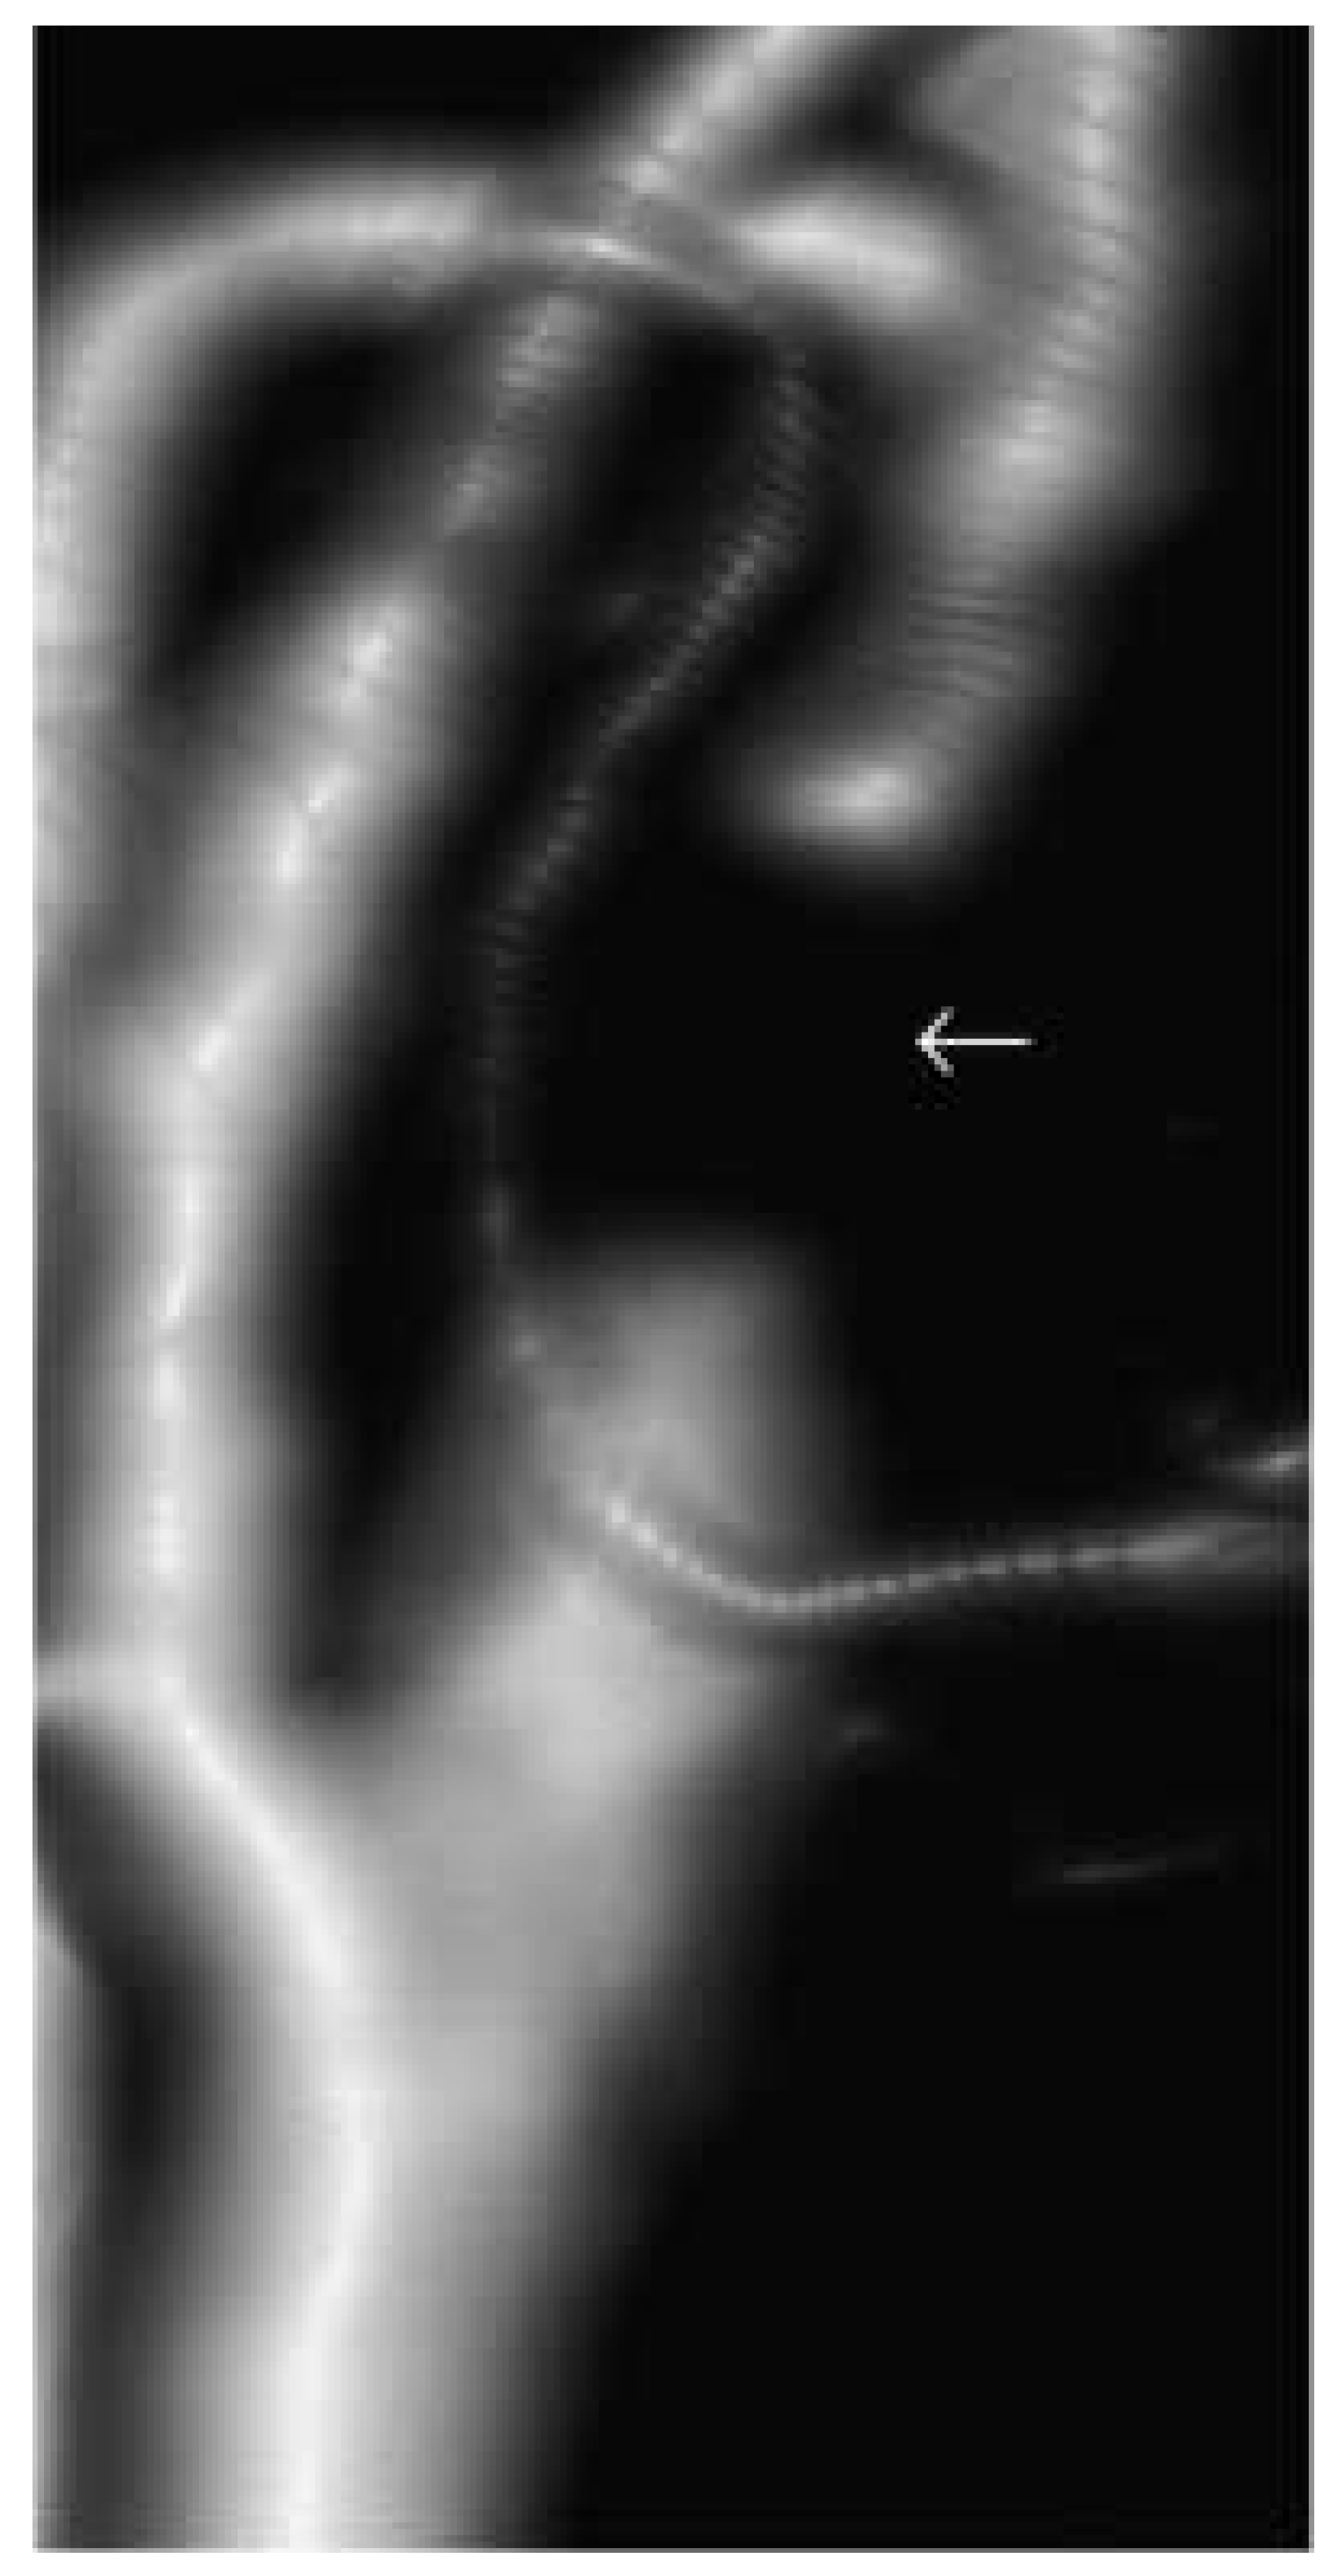

Die MR-Angiographie

|